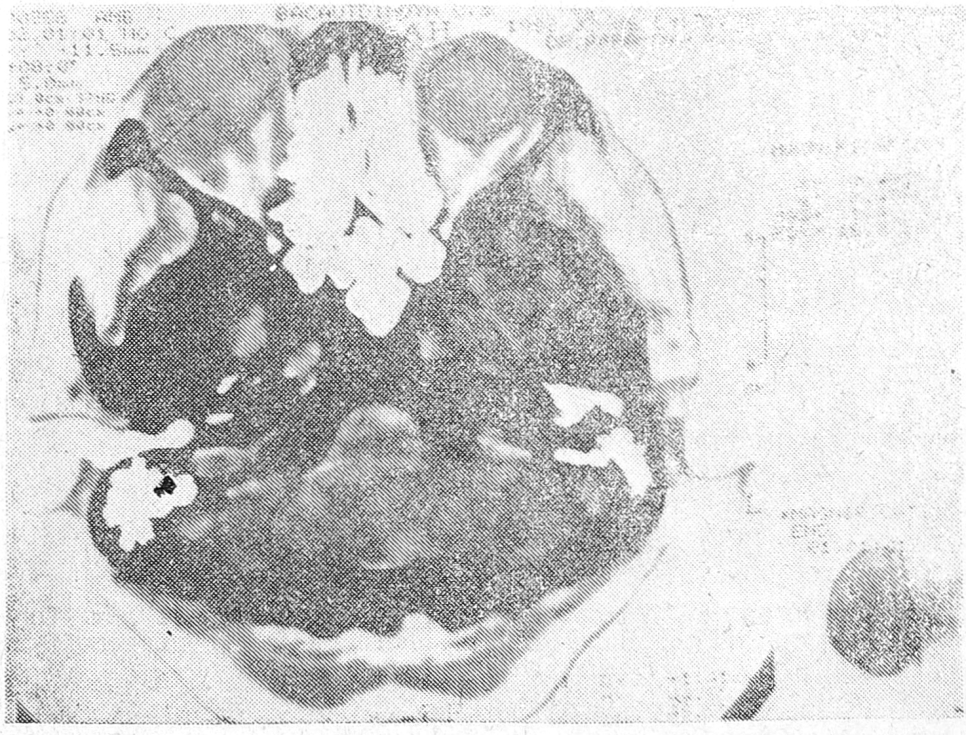

Приводим томограмму больного Н., 59 лет, с кровоизлиянием в головной мозг (рис. 5). Определяемая на ней гиперденсивная зона обусловлена кровоизлиянием в полушарие мозга.

Рис. 5. Томограмма головного мозга больного Н., 59 лет. Определяется кровоизлияние в головной мозг с прорывом в желудочки.